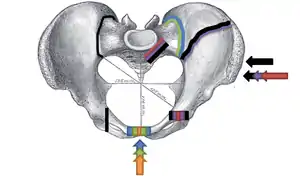

Young-Burgess classification

The Young-Burgess classification system is based on mechanism of injury: anteroposterior compression type I, II and III, lateral compression types I, II and III, and vertical shear,[5] or a combination of forces.

Lateral compression (LC) fractures involve transverse fractures of the pubic rami, either ipsilateral or contralateral to a posterior injury.

- Grade I – Associated sacral compression on side of impact

- Grade II – Associated posterior iliac ("crescent") fracture on side of impact

- Grade III – Associated contralateral sacroiliac joint injury

The most common force type, lateral compression (LC) forces, from side-impact automobile accidents and pedestrian injuries, can result in an internal rotation.[9] The superior and inferior pubic rami may fracture anteriorly, for example. Injuries from shear forces, like falls from above, can result in disruption of ligaments or bones. When multiple forces occur, it is called combined mechanical injury (CMI). The best imaging modality to use for this classification is probably a pelvic CT scan.

Open book fracture

One specific kind of pelvic fracture is known as an 'open book' fracture. This is often the result from a heavy impact to the groin (pubis), a common motorcycling accident injury. In this kind of injury, the left and right halves of the pelvis are separated at front and rear, the front opening more than the rear, i.e. like an open book that falls to the ground and splits in the middle. Depending on the severity, this may require surgical reconstruction before rehabilitation.[10] Forces from an anterior or posterior direction, like head-on car accidents, usually cause external rotation of the hemipelvis, an “open-book” injury. Open fractures have increased risk of infection and hemorrhaging from vessel injury, leading to higher mortality.[11]